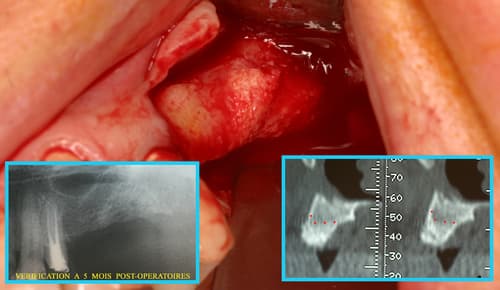

En complément des protocoles cliniques, cette approche peut contribuer à améliorer la cicatrisation, à condition de maintenir une hygiène bucco-dentaire rigoureuse.

Le laser peut également intervenir dans la préparation des sites osseux après extraction, afin de favoriser la régénération et préparer la pose implantaire.

Post-opératoire